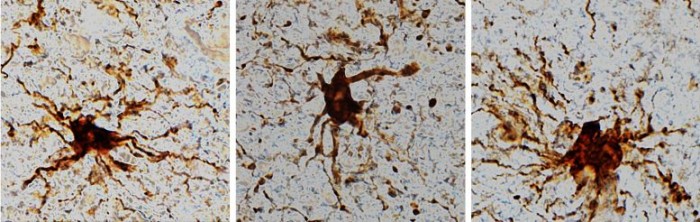

这些 "僵尸基因",即那些在死后间隔期后表达增加的基因是一种特定的细胞类型:被称为胶质细胞的炎症细胞。研究人员观察到,胶质细胞在死亡后的数个小时内持续生长并长出长臂般的附属物。

"胶质细胞在死亡后扩大并不太令人惊讶,因为它们是炎症性的,它们的工作是清理缺氧或中风等脑损伤后的物质,"UIC医学院的John S. Garvin教授和神经学和康复学负责人、论文的通讯作者Jeffrey Loeb博士说,但重要的是这一发现的意义:大多数利用死后的人类脑组织来寻找自闭症、精神分裂症和阿尔茨海默病等疾病的治疗方法和潜在疗法的研究,都没有考虑到死后的基因表达或细胞活动。